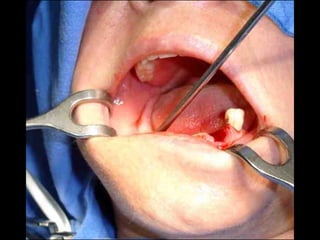

Segundo tiempo quirúrgicopara aplicar la estructura.

Estructura en íntimocontacto con la superficie ósea, quedando los postes fuera de la fibromucosa gingival..

En el modeloque se obtuvo en el primer tiempo quirúrgico se elabora en el laboratorio la estructura que se adptará al maxilar por mecanismo de grapa.